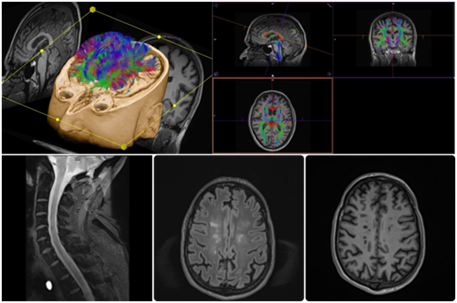

• structural MRI, diffusion tensor imaging (DTI) and DCE perfusion MRI in relapsing-remitting multiple sclerosis

MRI-1

• advanced neonatal neuroimaging in pre-term babies with necrotizing enterocolitis (NeuroNEC)

• investigating brain networks in neonates with hypoxic ischemic encephalopathy using MRI

• investigating proximal interphalangeal finger joint biomechanics using MRI and CTMRI 3

MRI-3